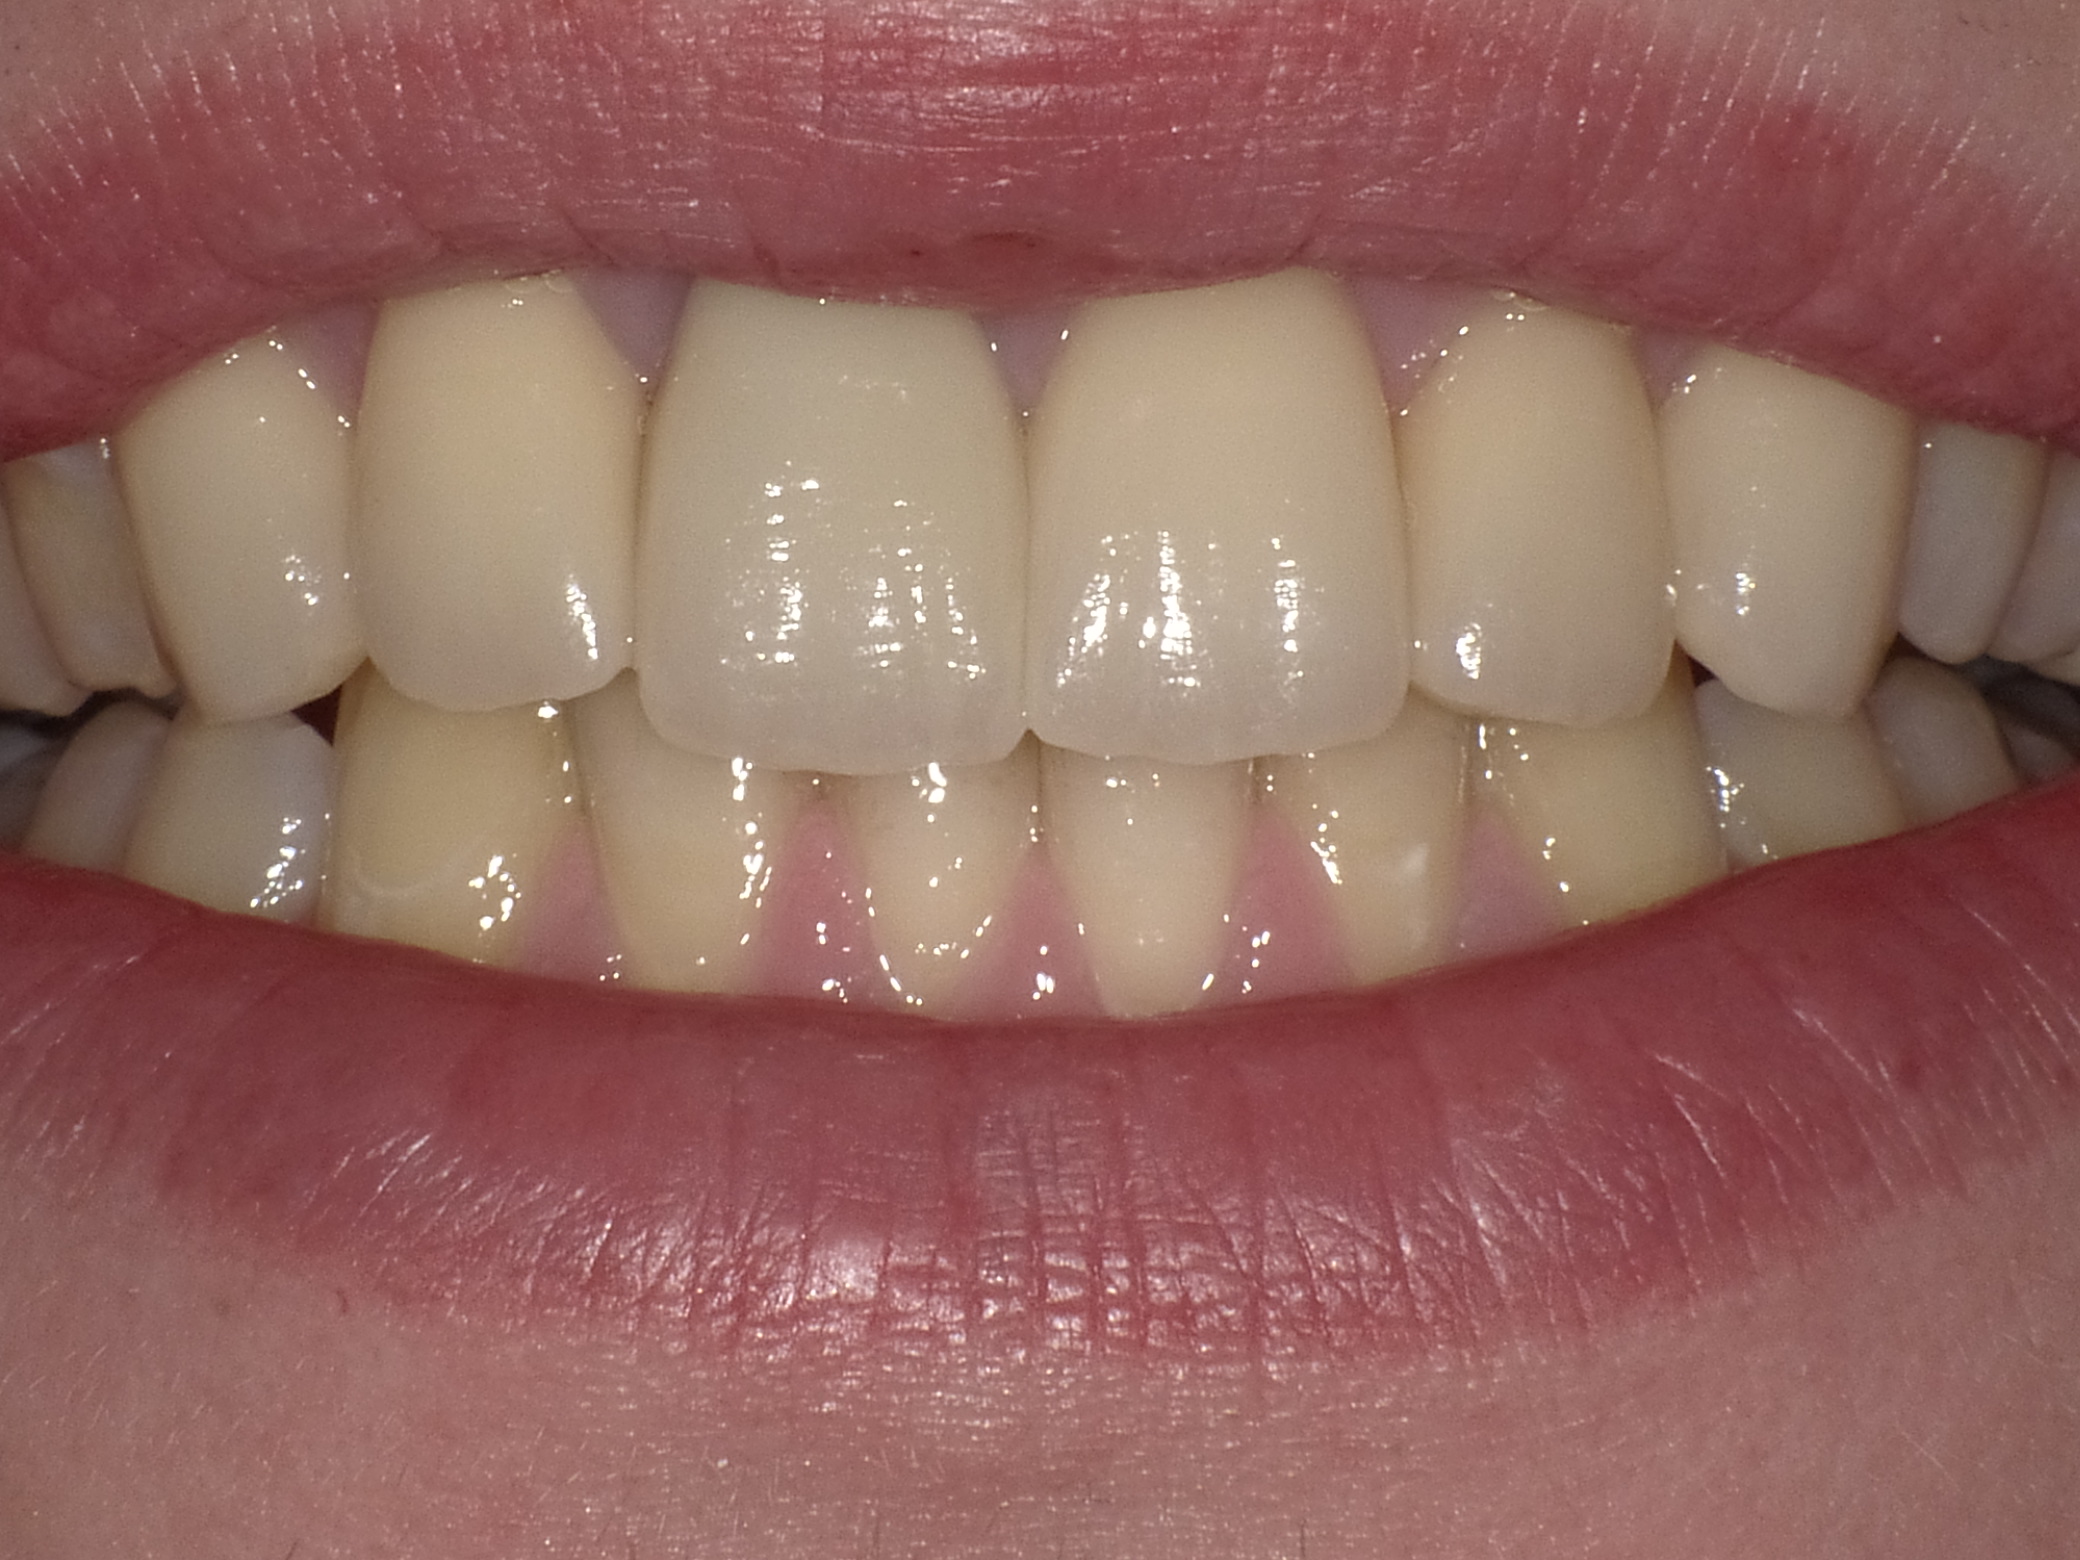

Patientin mit dem Wunsch nach ästhetischer Optimierung der Gesamtsituation

Vorher: Patientin mit dem Wunsch nach ästhetischer Optimierung der Gesamtsituation

Ergebnis nach nur 2 Langzeit-Behandlungsterminen mit vollkeramischen Veneers und Kronen

Nachher: Ergebnis nach nur 2 Langzeit-Behandlungsterminen mit vollkeramischen Veneers und Kronen